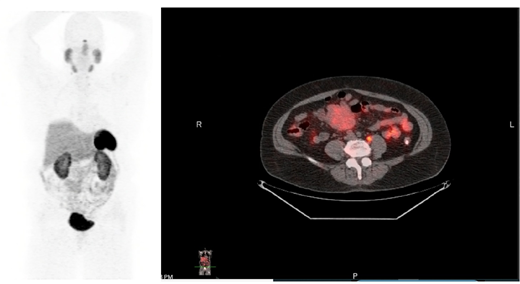

A GA-68 dotatate PET/CT showed uptake within the known mesenteric mass, most likely representing carcinoid tumor. Minimal uptake observed in retroperitoneal lymph nodes felt to represent early metastatic disease.